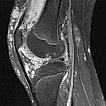

Hier sagittale Ansicht einer MRT (T2-Wichtung mit Fettsättigung) des rechten Knies. Die venöse Malformation ist deutlich hyperintens (weiß im Bild) und erstreckt sich bis intraartikulär. Zudem ausgedehnter Knorpelschaden.